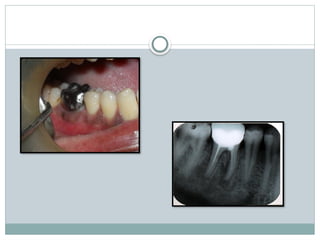

Clinical diagnosis

Radiographic diagnosis

Grade-lV:

 Interdental bone is completely

destroyed

 Soft tissue is resided completely, so

furcation opening is clinically visible

 Tunnel exist between the roots